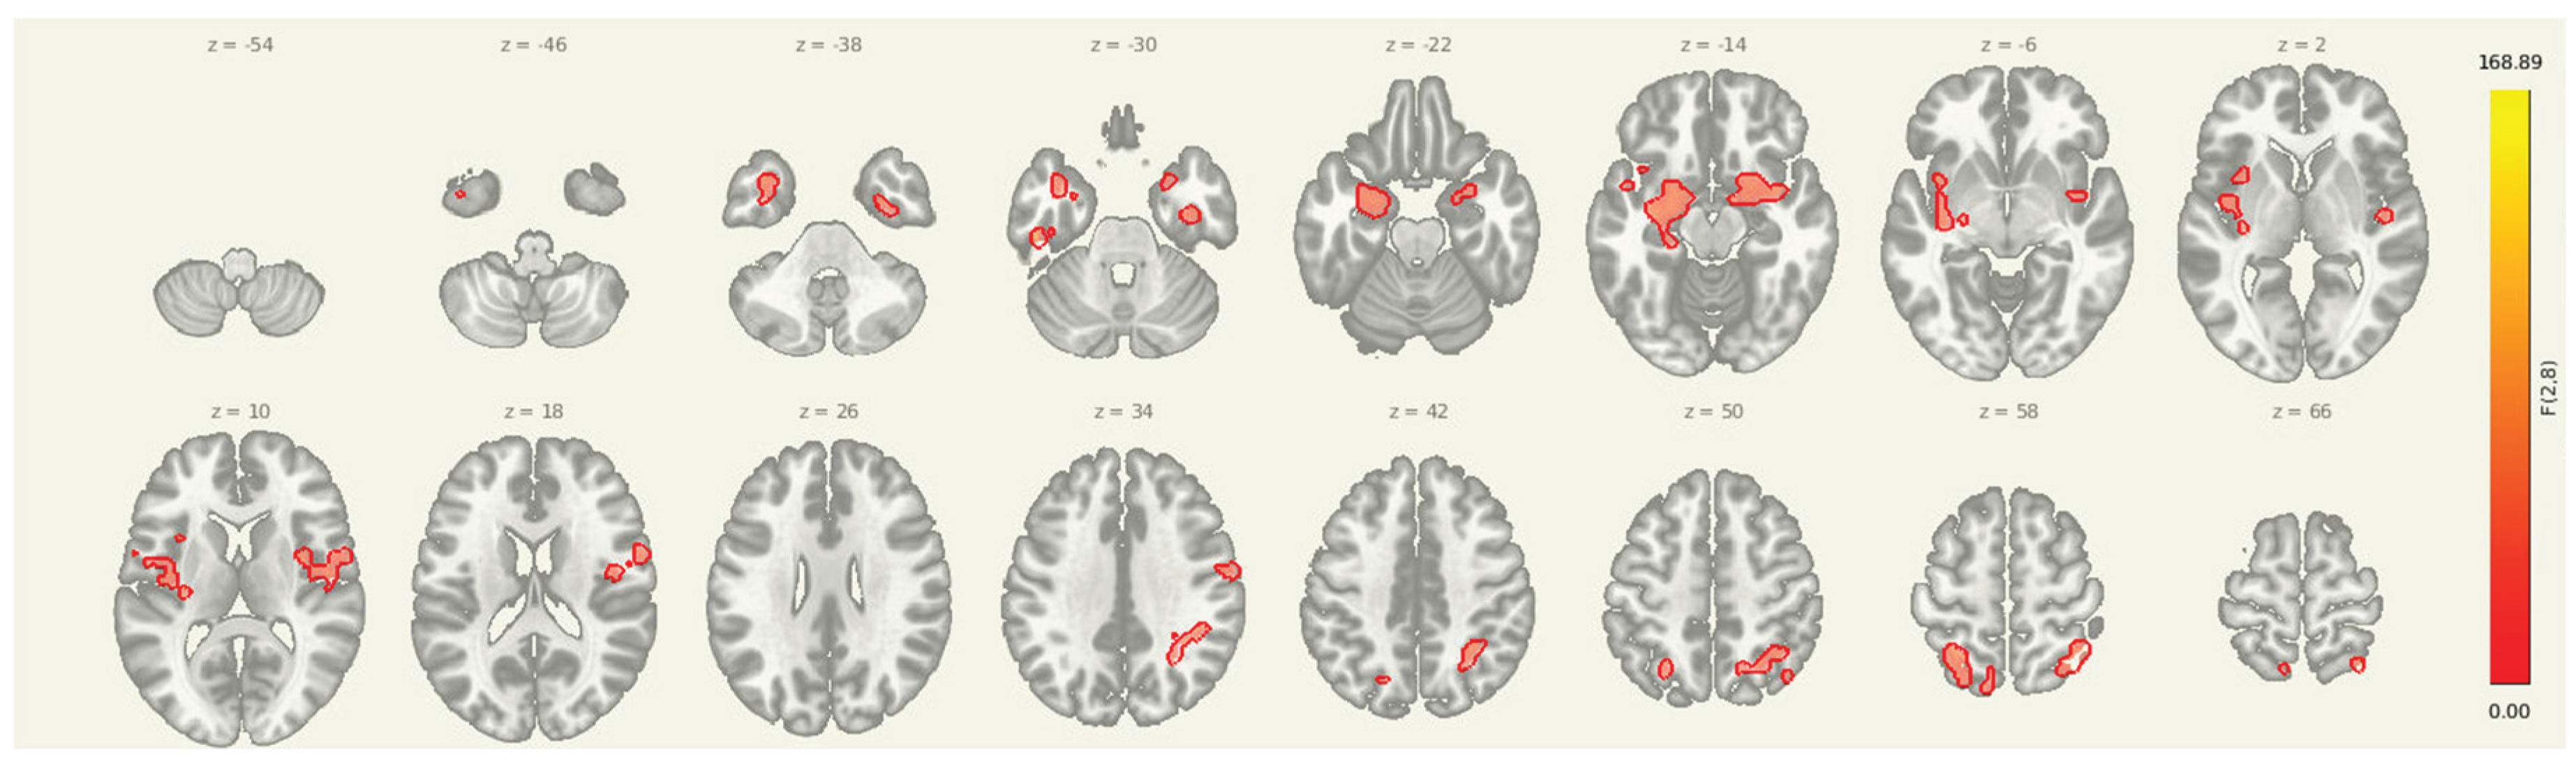

Prior to intervention, seed-to-voxel analysis from the amygdala revealed widespread connectivity with multiple cortical and subcortical regions. Significant clusters were observed in bilateral sensorimotor and frontal areas, including the left parahippocampal gyrus (MNI: -36, +06, -28; cluster size = 1396 voxels; p-FDR < 0.001), right superior parietal lobule (+38, -56, +60; 575 voxels; p-FDR < 0.001), right insular cortex (+46, -06, +16; 406 voxels; p-FDR < 0.001), and right thalamus (+18, +10, -16; 383 voxels; p-FDR < 0.001). Additional clusters were detected in the left superior parietal lobule, right cerebellum, and prefrontal cortex, further supporting elevated amygdala connectivity within regions implicated in sensory integration, emotional processing, and motor readiness.

Pre Amygdala Seed

Figure 1. Pre-intervention amygdala connectivity map. A 3D surface rendering illustrates widespread resting-state functional connectivity from the amygdala seed at baseline. Significant clusters were observed in bilateral cortical and subcortical regions, including the left parahippocampal gyrus, right superior parietal lobule, right insular cortex, and right thalamus (all p-FDR < 0.001).

Figure 2. Multi-slice view of amygdala seed connectivity at pre-intervention. Displayed clusters correspond to those reported in Table 2, showing significant resting-state connectivity between the amygdala and bilateral cortical regions, including sensorimotor and prefrontal cortices. All results are thresholded at p-FDR < 0.05 and shown in MNI space.